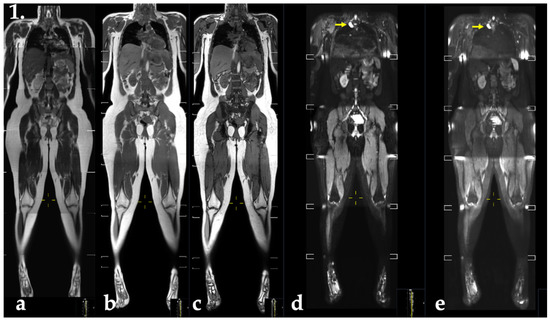

2.4. MRI

2.5. Evaluation